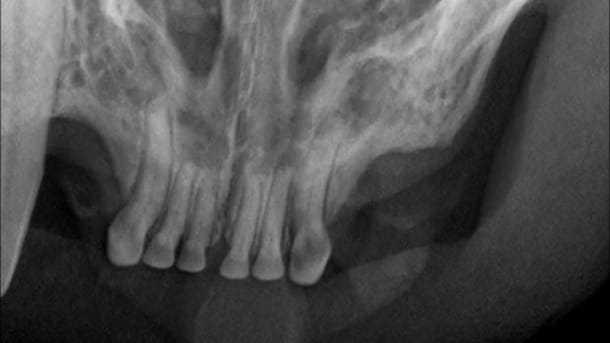

• Cat dental X-ray

At VCA Peone Pines Animal Hospital, we are passionate about your pet’s oral health. Our doctors have pursued advanced training from Veterinary Dental Specialists to provide the knowledge and experience to address your pet’s dental concerns. You won’t find a veterinary team more dedicated to ensuring that your pet’s mouth is as healthy as possible.... Read more

• Dogs and cats don't often get cavities. But they do frequently suffer from other types of dental disease. Periodontal or gum disease, in fact, is the number one illness found in both dogs and cats.... Read more

• Our veterinarians offer periodontics to help slow periodontal disease and tooth loss.

Periodontal disease is a major cause of tooth loss in dogs and cats. Periodontics involves the diagnosis and treatment of diseases of the tissues that surround the teeth.... Read more